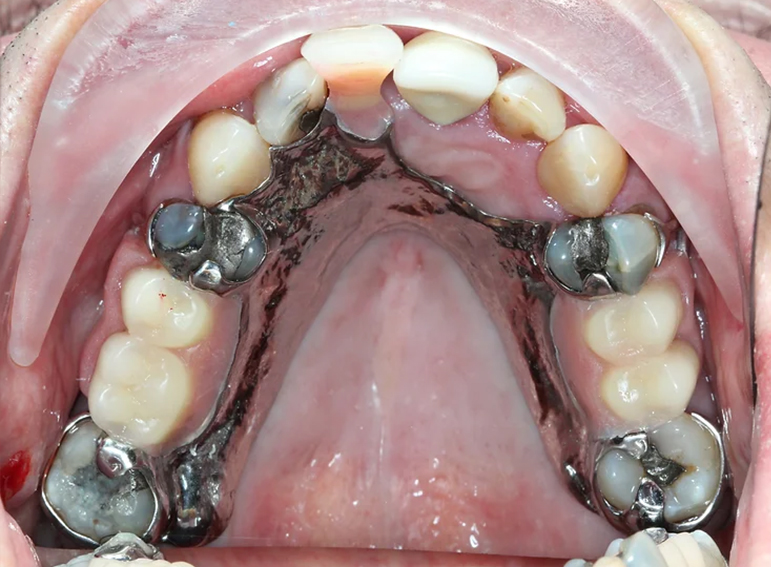

Complex upper and lower denture after oral cancer.